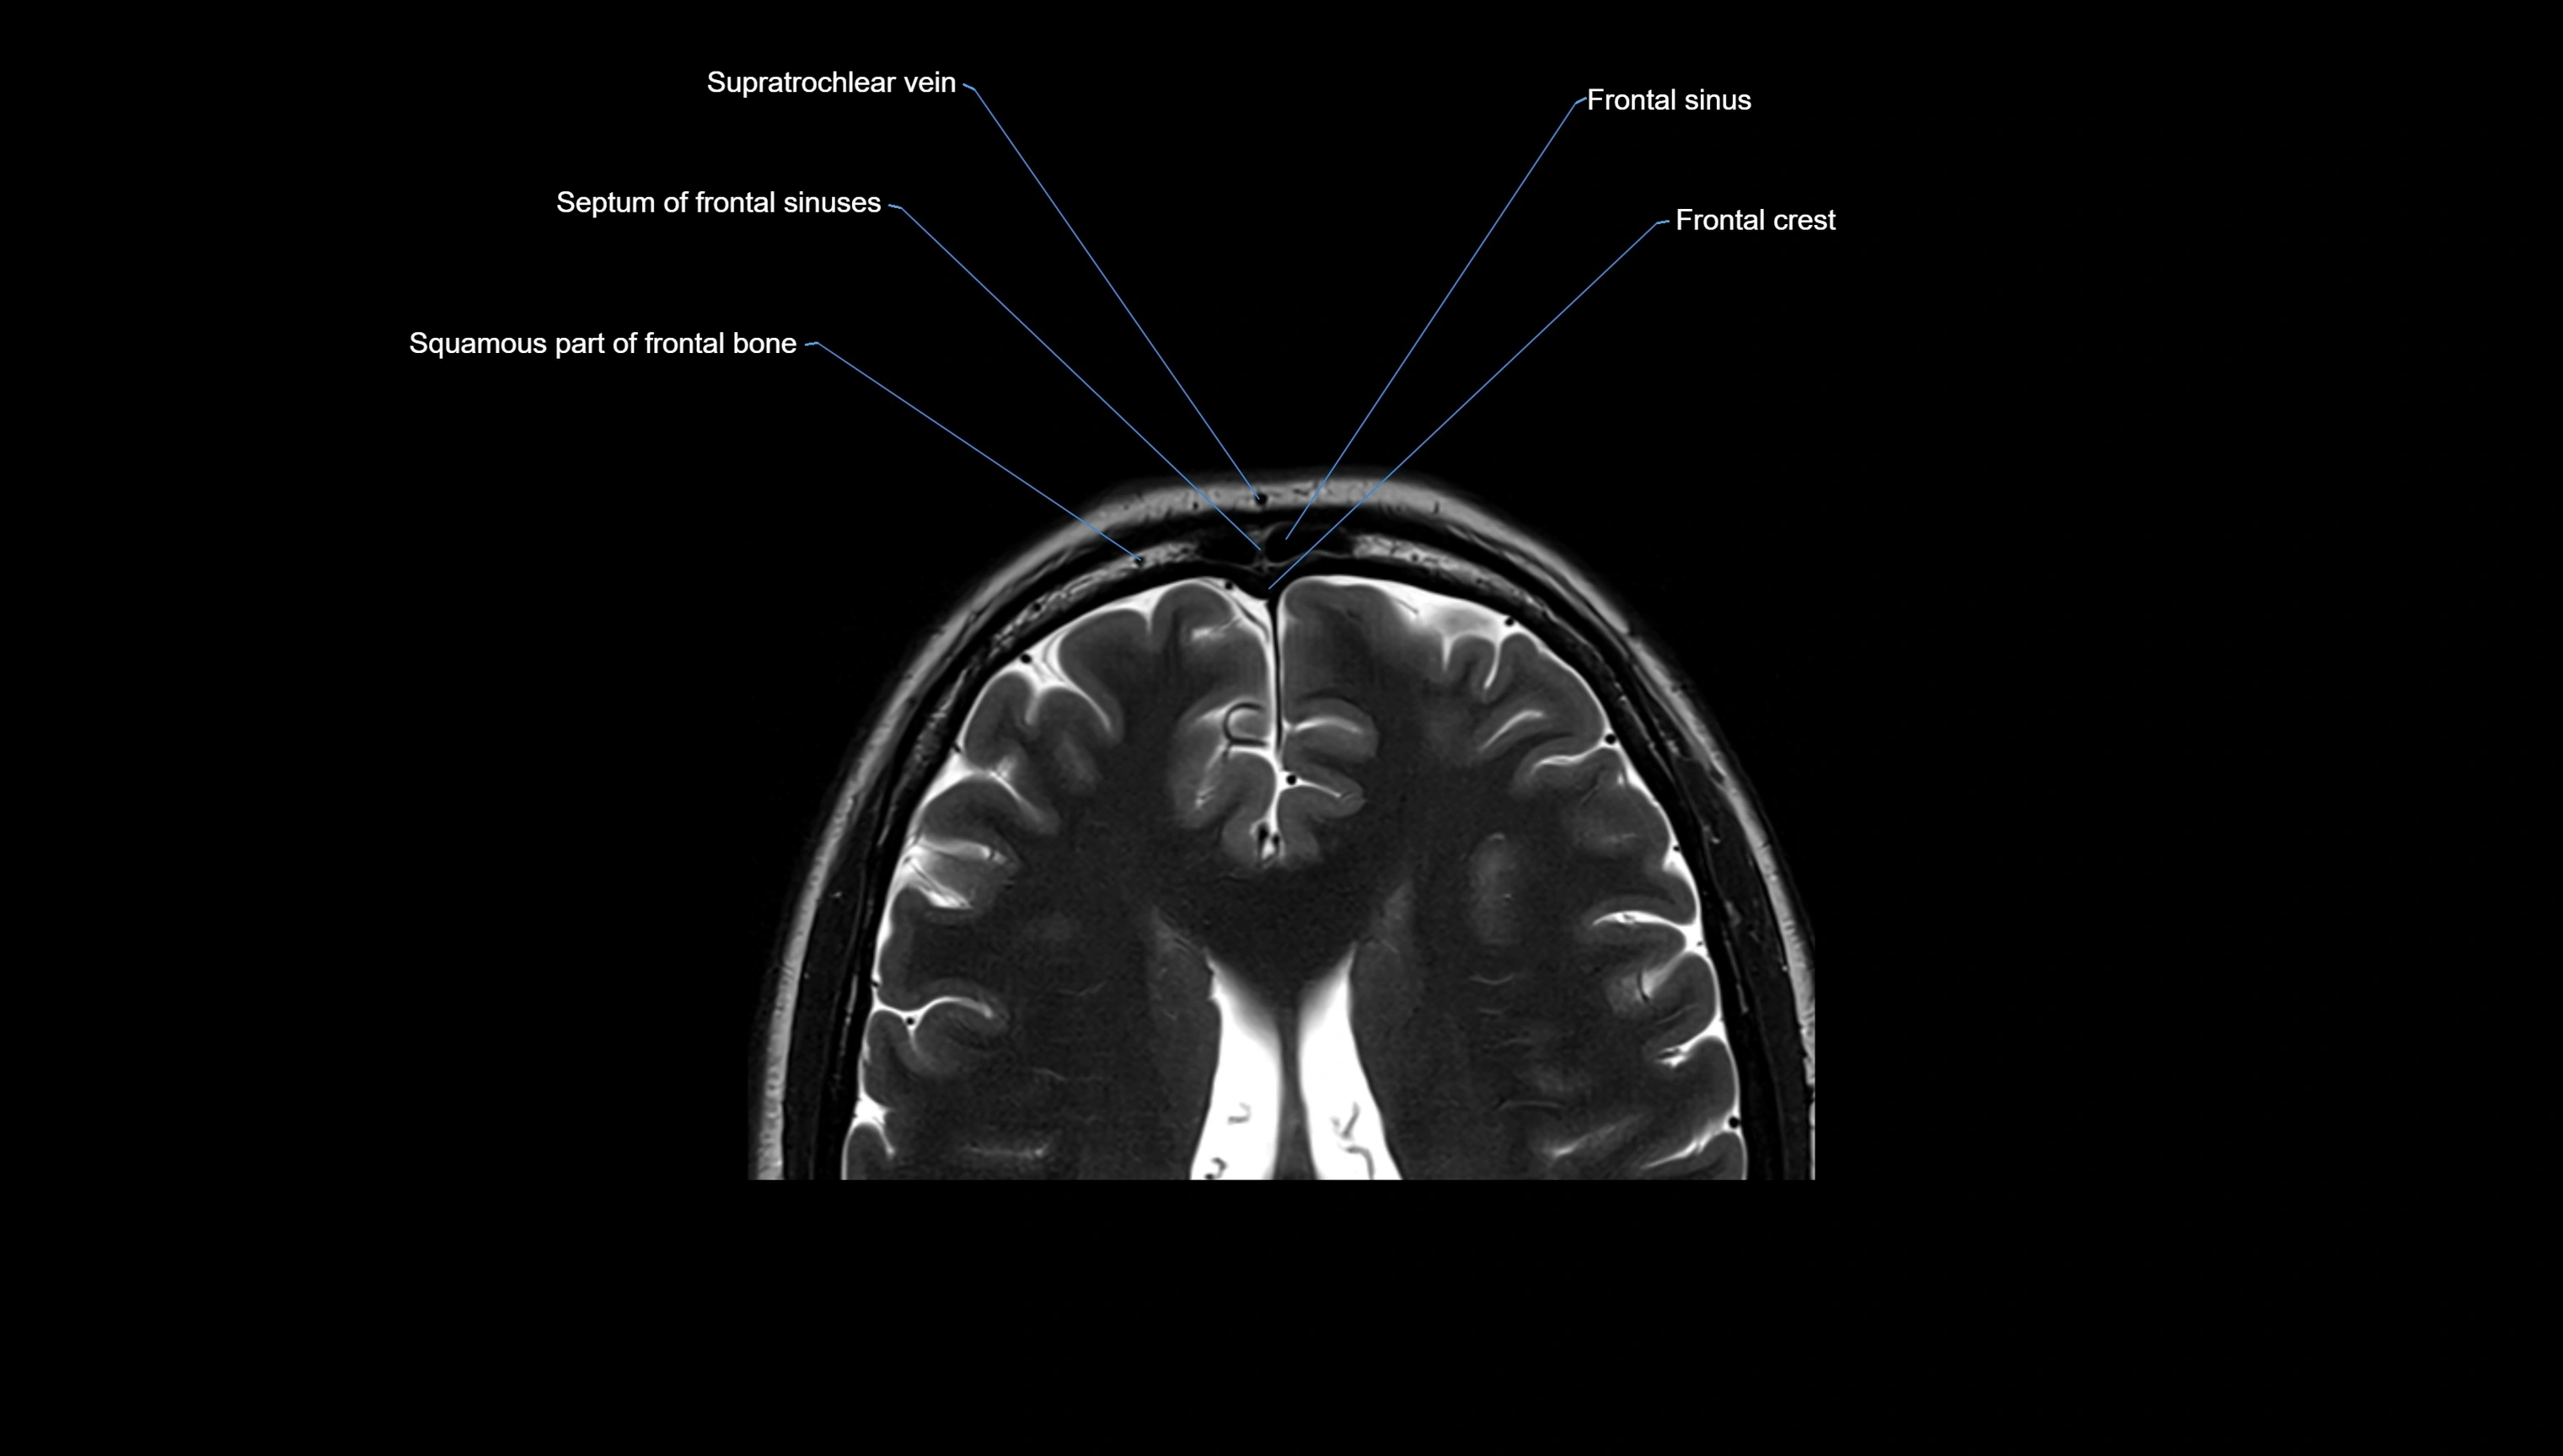

MRI images